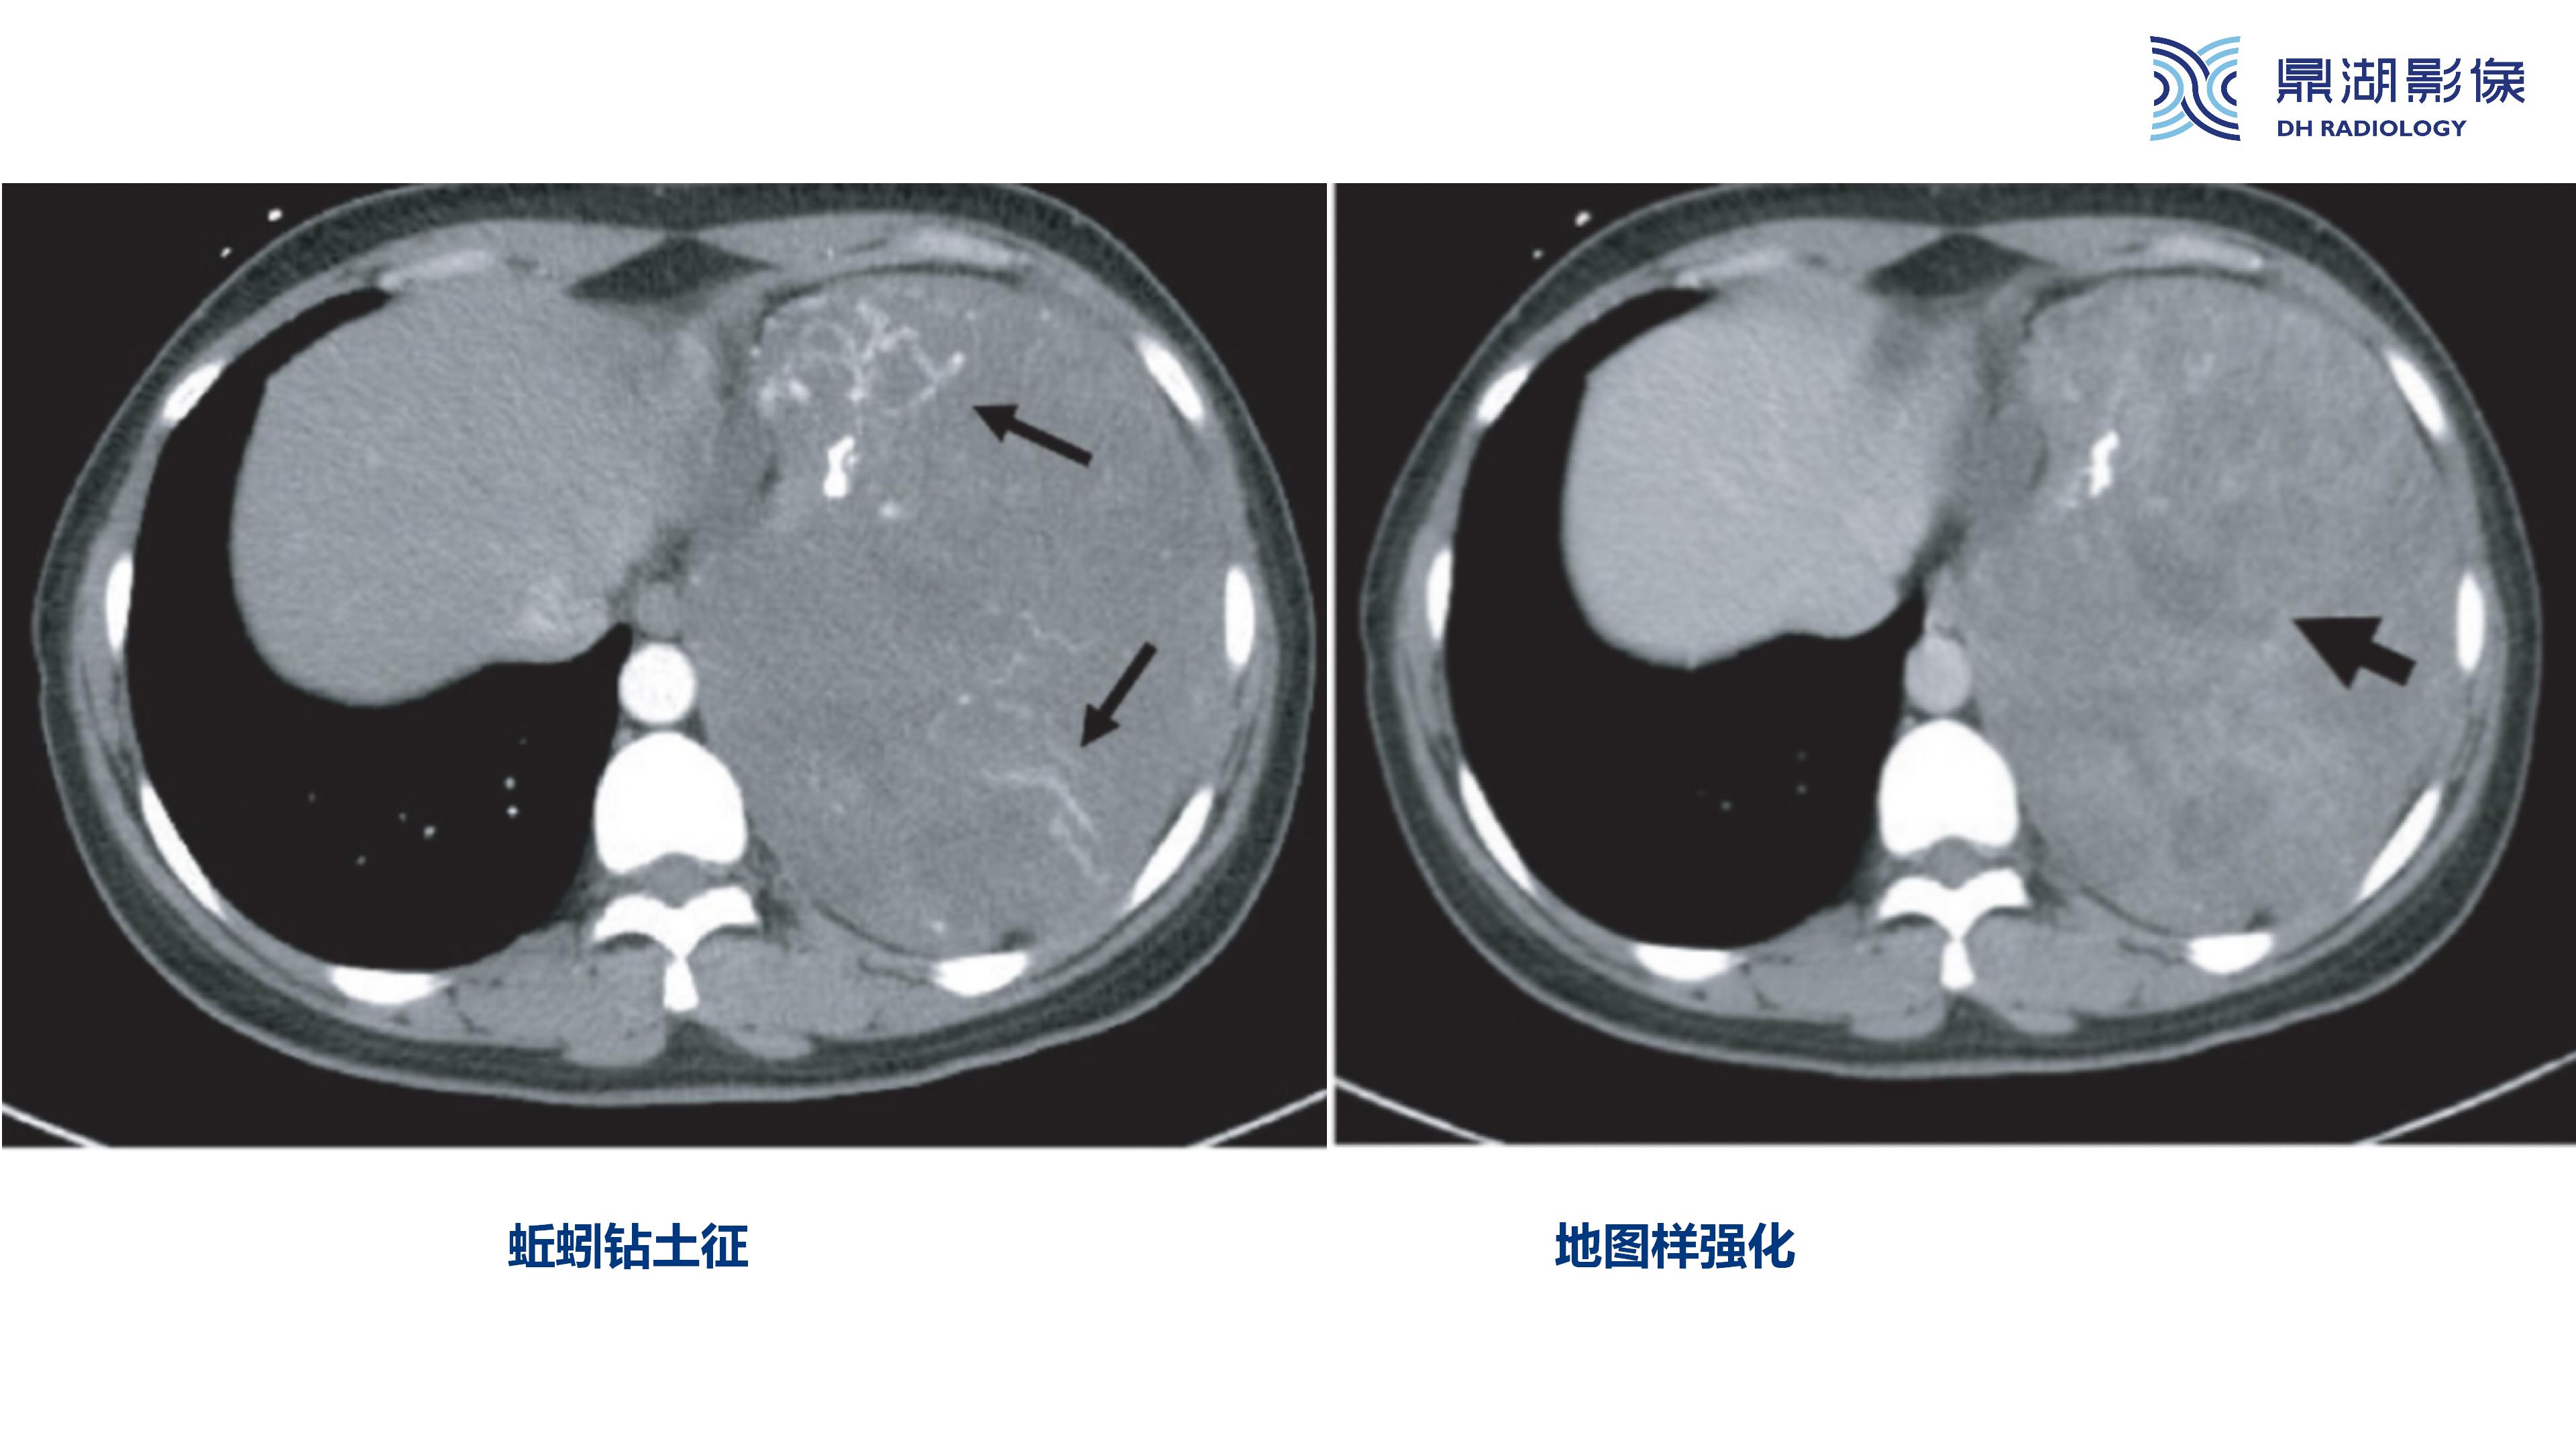

纵隔血管瘤-鼎湖社群读片病例